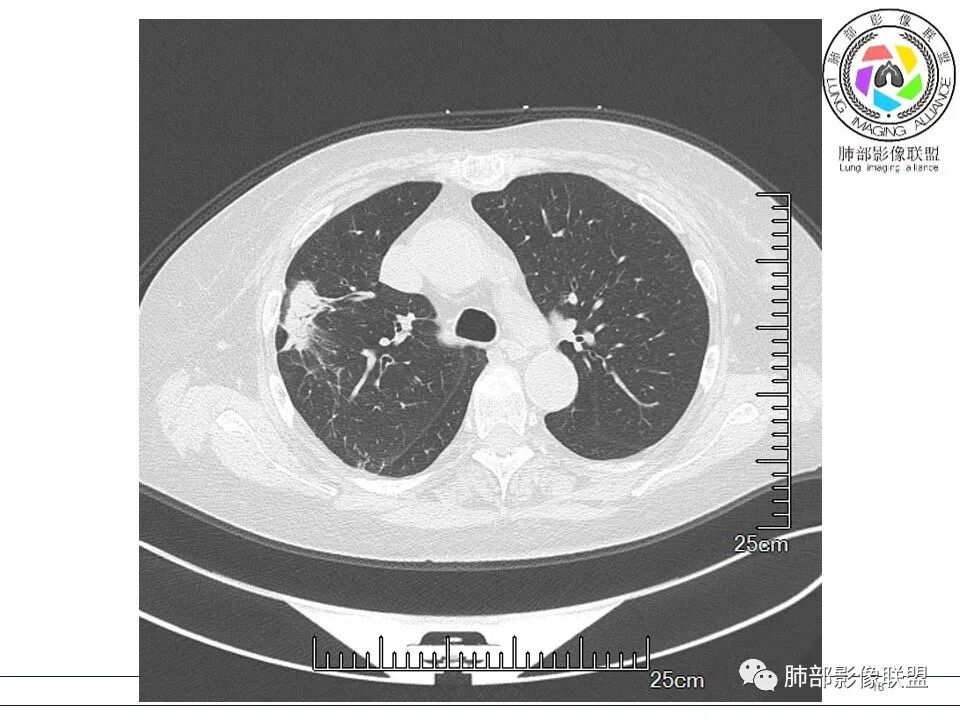

小兜: 晨读,女,70岁,风湿性多肌痛病史一年,半月前体检发现肺部阴影,无症状,口服药物治疗。现片示:右肺胸膜下条形实变影,局部层面似见多结节融合,周边伴条索影。下方近叶间胸膜处斑片状实变影伴条索影,宽基底与胸膜相连。综合考虑为炎性病变,隐球菌或OP可能

衡妈: 老年女性,右肺上叶沿胸膜下不规则实性病灶,长轴平行于胸膜,有结节融合感,边缘部分彭隆部分平直,周围可见数条纤维灶影,病灶内可见充气支气管征未达远端,首诊考虑慢性炎性肉芽肿,隐球菌?机化性肺炎?建议增强扫描及ct下穿刺活检。

晨读:女,70,未诉症状。风湿性多肌痛病史,口服强的松等药物治疗。胸部CT:右肺上叶多发不规则斑片影,沿支气管分布,部分病灶侧向融合、平行于胸膜,边缘平直内收为主、部分彭隆,周围模糊晕、可见数条纤维灶影,胸膜牵拉,病灶内可见充气支气管征、管腔不畅,考虑慢性炎症,PC?OP?鉴别腺Ca、SCLC等。

5、分布:隐球菌肺炎是肺泡性炎症,病灶分布多位于胸膜下,可紧贴胸膜,也可与胸膜邻近,病灶长轴与胸膜平行。(划重点,分布特点非常重要,因为隐球菌如果没有荚膜,会被巨噬细胞吞噬,在人体内是无法生存。隐球菌孢子吸入后,要有高浓度的CO2的条件下,才能形成荚膜,所以肺泡内、胸膜下多见)

10、“葫芦兄弟”:邻近胸膜多发结节,形态接近,排列呈长串状。